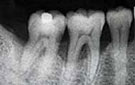

歯周病の治療方針

歯周病はバイオフィルムという歯周病菌の塊が歯根にへばりつき毒素をばらまき、歯を支える骨を知らないうちに溶かす怖い病気です。キッチンの流しで食器を毎日洗っていると排水溝にヌメリが付きます。しっかりスポンジで洗い流してツルツルしてもしばらくするとまた汚れます。同じようなことが私たちのお口の中でも起こっています。毎日歯を磨いていても歯ブラシの届かない歯茎の中は歯周病菌が集まって棲みつくのです。